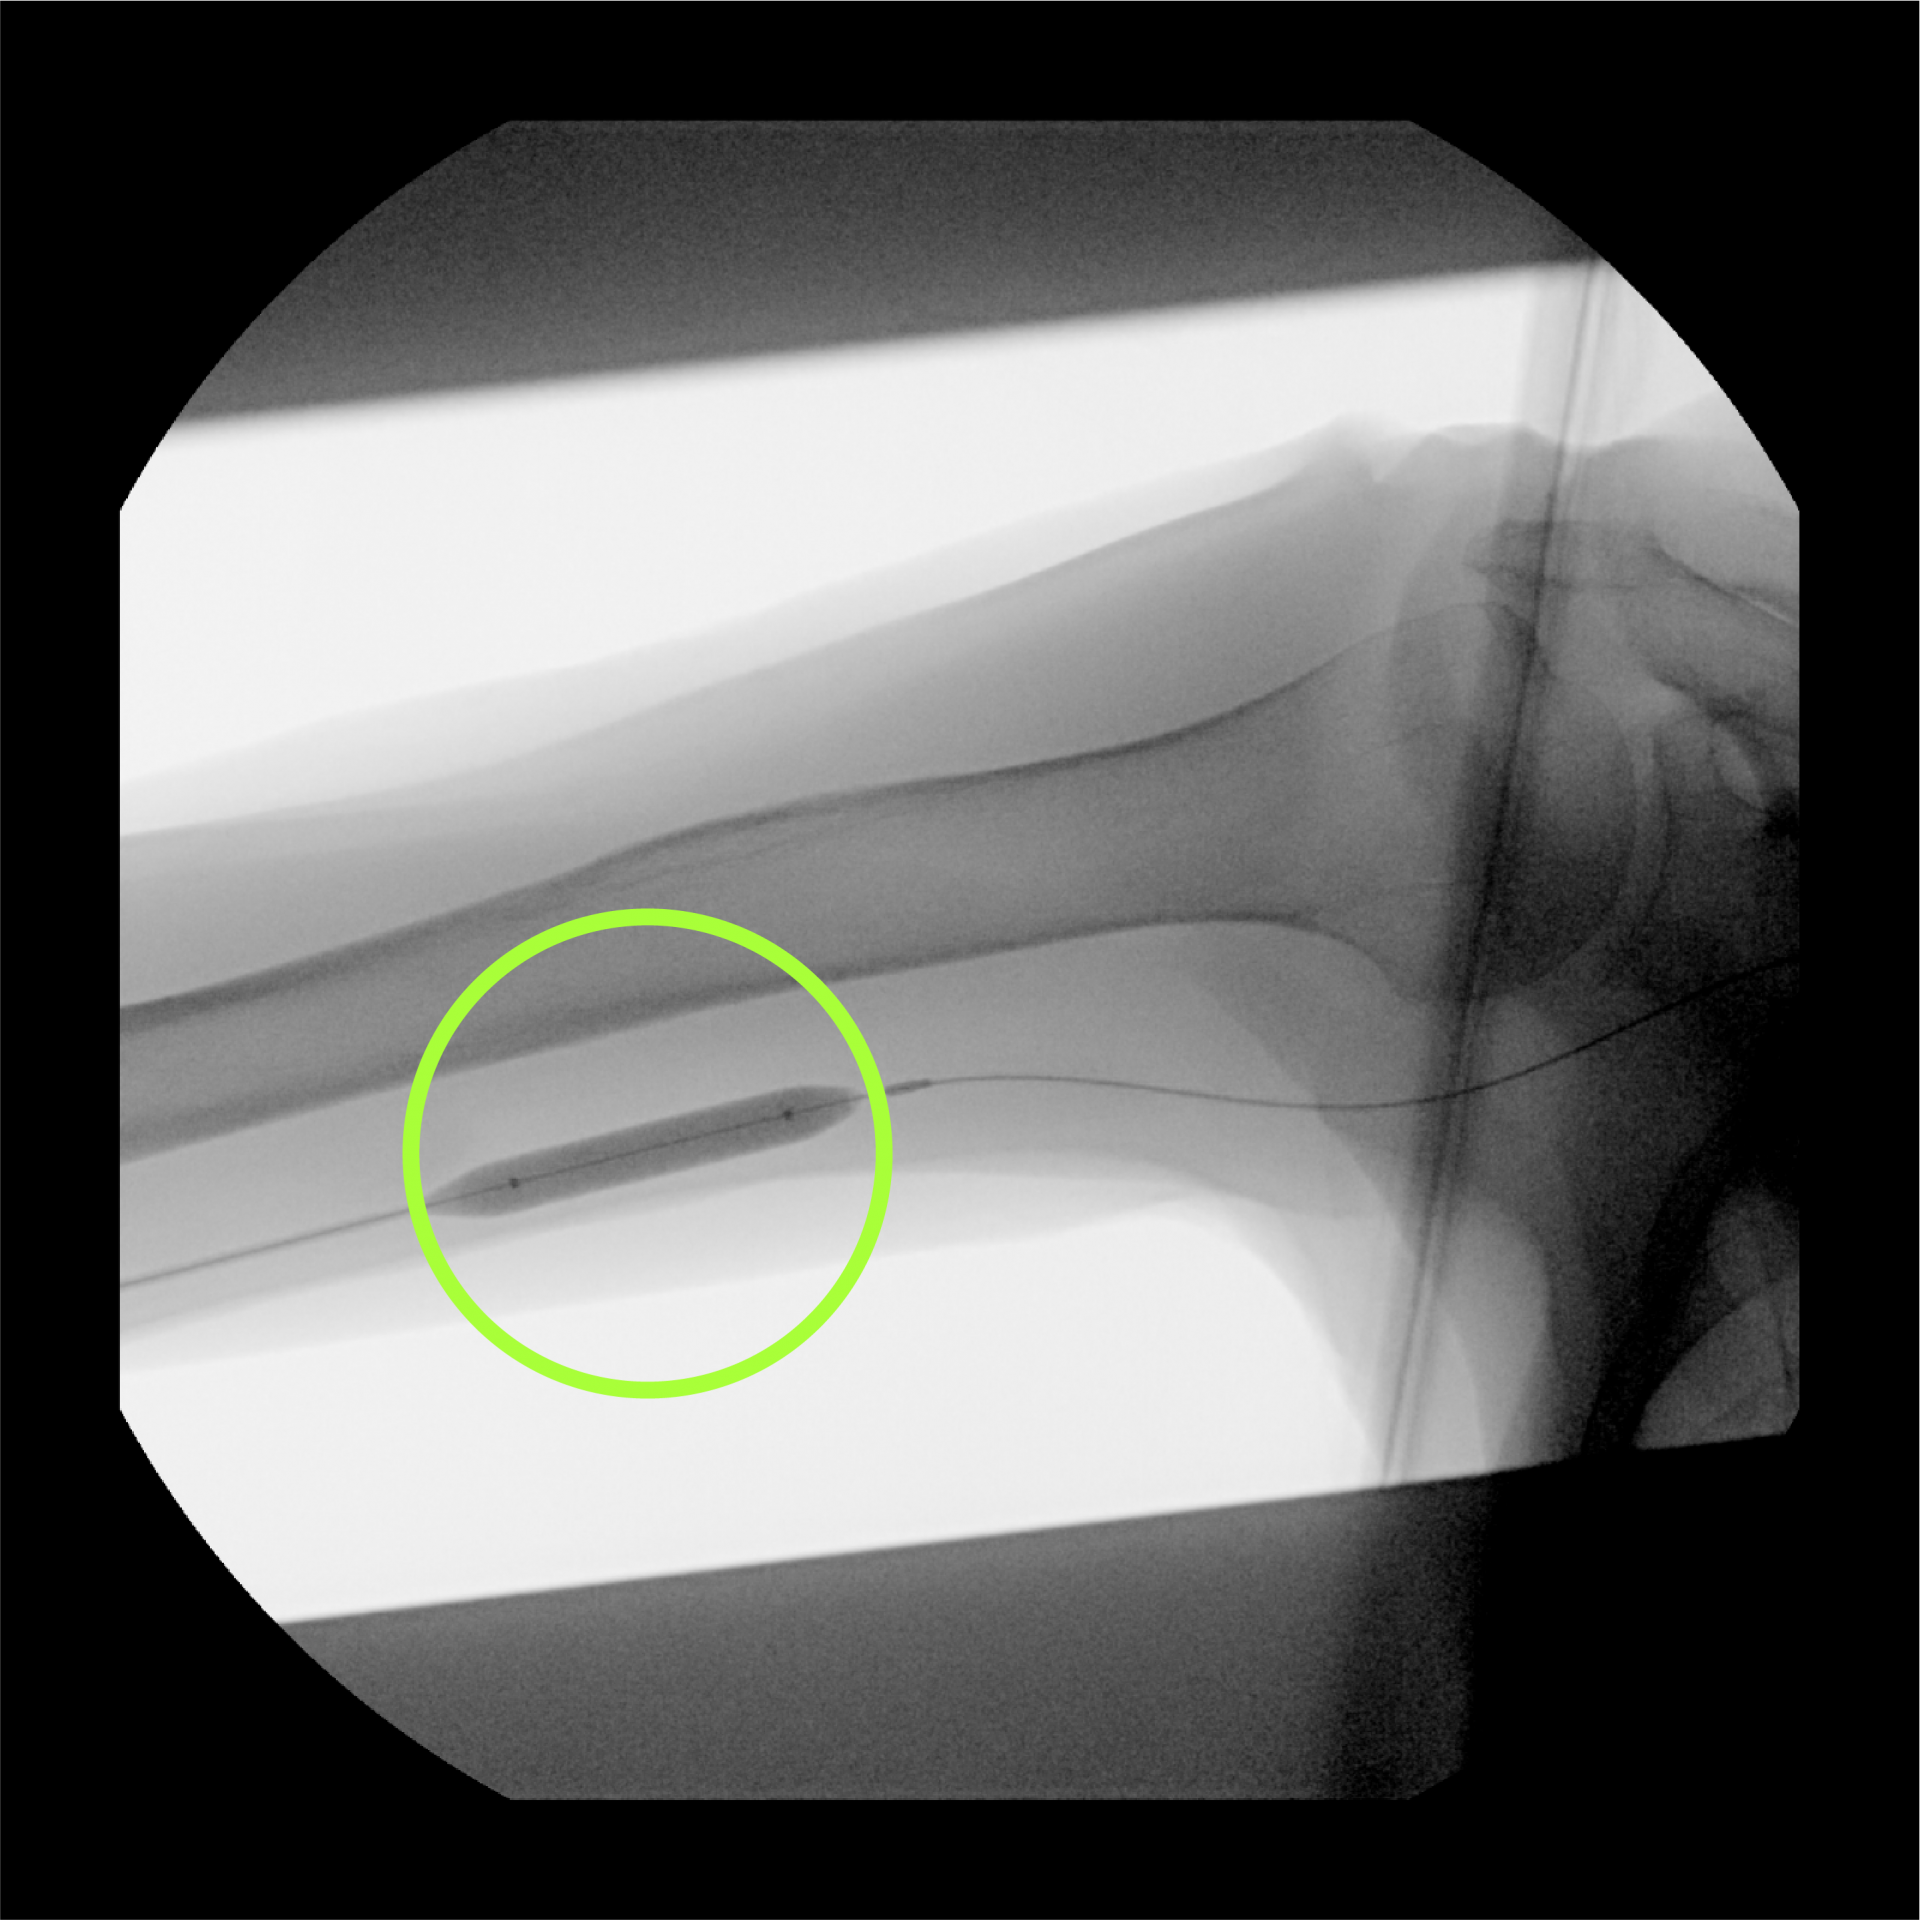

축소술 전의 모습

1 축소술 전

축소술 후의 모습

2 축소술 후